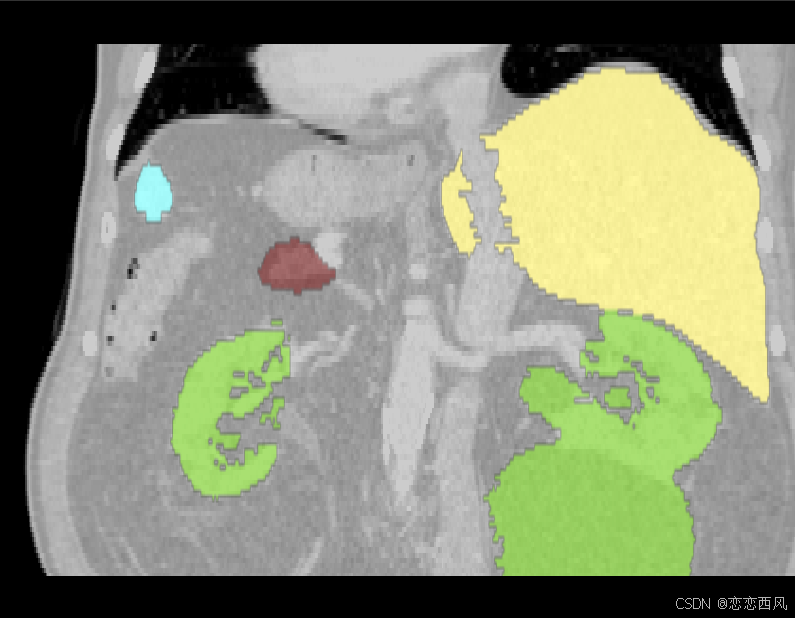

医学图像 三维重建,原图与灰度图叠加,原图与多图叠加显示;多图像融合显示,彩色灰度图像融合

我们在做图像分割或融合时,有时需要显示多份数据进行叠加显示;可能需要这种效果:

2.2 显示多个mask 数据;

2.3 显示原图与多个 mask 数据;这个也有问题原图显示成了蓝色,没办法显示成灰色

1.通过mask进行三维重建模型,并用不同颜色显示;

2.原图与mask数据进行叠加显示,原来与灰度图像使用多种颜色区分显示;